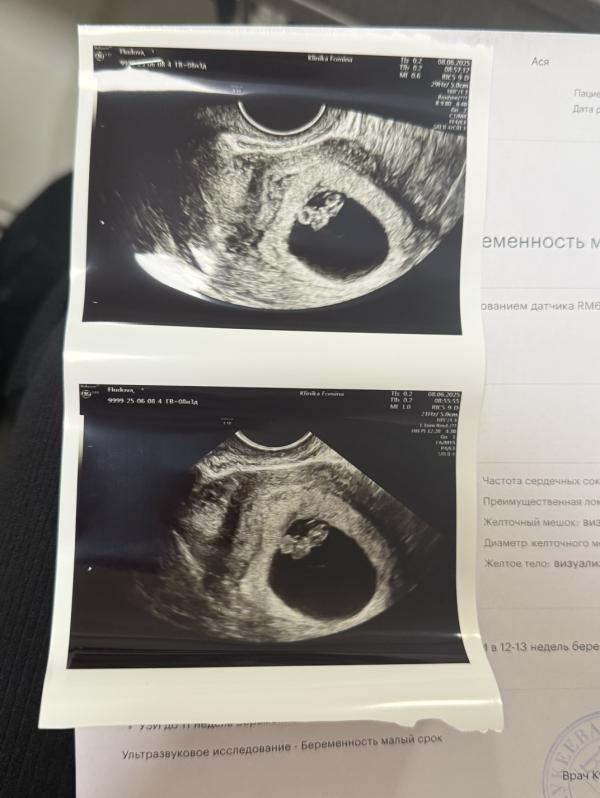

Сегодня нам 9 недель

В воскресенье была на узи, уж очень сильно болел живот, спина и ноги, начала переживать 😬

Но с Веномом все хорошо, растем и радуемся 🥰